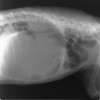

●胃捻転の正式名称は、英語でGastric Dilatation-Volvulusと言い、和訳では胃拡張-

胃軸捻転症である。獣医師間では略してGDVと言う。通常、人や猫では遭遇しない疾患である。

●空気を伴う劇的な胃の拡張があり、急変して来院する。そして、その殆どが捻転を伴っている。90~360度捻転するため、放置すれば、その程度により数時間内で死亡する。

●GDVは急性の、死が切迫した疾患であり、緊急処置を要する。早期の発見と治療開始が救命の基本である。胃拡張は胃の膨張のためであり、通常は嚥下した空気と胃内容物で充満される。胃拡張は胃軸捻転によって悪化する場合がある。

●GDVは胃がその長軸で捻転した時に起こり、これが胃からの流出の完全な閉塞をもたらす。同時に起こる胃-食道吻合部(噴門)の閉塞は嘔吐やおくびによる胃内のガスや内容物(胃内液体)の蓄積減少を不可能にする。

●症状は鼓腸を伴う腹囲膨満で、急性に発症する。嘔気を催すが、ガスや内容物の嘔吐を伴わない。その他に流涎、落ち着かない、呼吸困難などの症状がある。